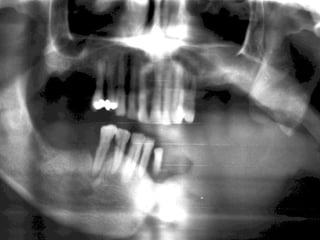

26 - Pacientedo sexo feminino, 30 anos de idade, se apresentou com aumento de volume no corpo da mandíbula, região dos dentes 45, 46 e 47, assintomático e com evolução de aproximadamente 1 ano. Pelo exame clínico constatamos expansão óssea e deslocamento dos dentes 45 e 46 de suas posições normais. Através de radiografia panorâmica observamos uma imagem radiográfica multilocular onde as trabéculas ósseas se encontravam perpendicularmente umas às outras e em outras regiões com aspecto de bolha de sabão. Com base no quadro clínico, o diagnóstico é: a) Ceratocisto e mixoma odontogênico. b) Odontoma composto e ameloblastoma. c) Mixoma odontogênico e ameloblastoma. d) Mixoma odontogênico e odontoma composto. e) Ameloblastoma e ceratocisto.

Ameloblastoma Freqüência: -1%de todos os cistos e tumores dos maxilares - Maior ocorrência entre a segunda e a quinta décadas de Vida (picos entre 35 e 45) -80% ocorrem na mandíbula -Área de molares inferiores, ramo ascendente de mandíbula. -Na maxila: molares superiores, seios maxilares e assoalho da fossa nasal (TOMMASI e FERNANDES, 2002)

Mixoma Freqüência: -Segunda e terceira década de vida -Atinge pouco mais a maxila que a mandíbula (região posterior + frequente)

Exame complementares RadiografiaPanorâmica; Radiografia Oculsal; Teste de Vitalidade; Punção Exploratória; Biópsia incisional.

Teste de VitalidadeDente 43: Negativo Dentes 42,44 e 45: Positivo.